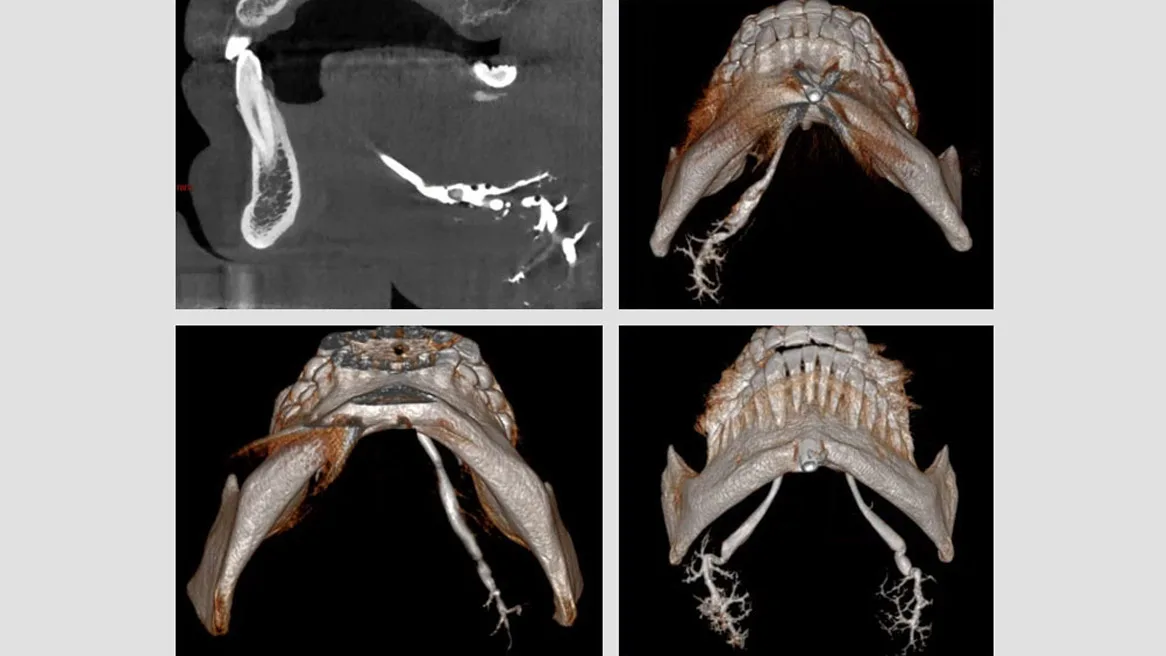

Sialographie 3D CBCT, Sialo CBCT décrite par Drage et Brown

Lithiases, sténoses et dilatations canalaires, sialodochites chroniques, anomalies anacroniques

Diagnostic radiologique et cartographie canalaire

Résultats : lésions retrouvées. Lithiases, sténoses. Sialodochite chronique (vacuoles multi-intraparenchymateuses, calcifications distales, aspect d’arbre mort distal)

plicature anatomique des canaux de Wharton

Autres résultats : exploration canalaire jusqu’aux divisions IV.

Résolution non altérée par des artefacts métalliques et dentaires

Avantages : facile, accessible, peu onéreuse. Reconstruction multiplanaire et 3D. Diamètre et perméabilité du canal exécréteur. Nombre, localisation, taille des lithiases. Guidage du geste endoscopique.